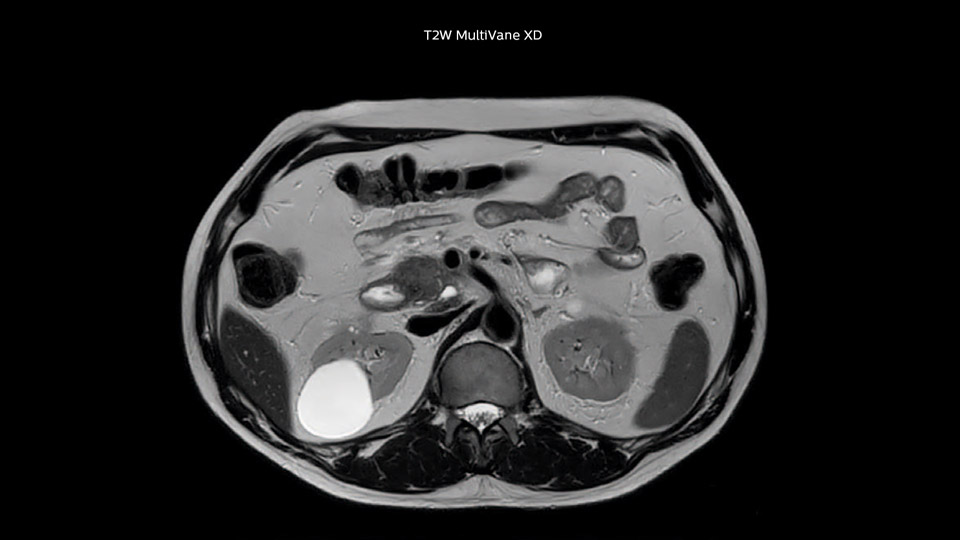

“With MultiVane XD we get excellent motion-corrected images with high spatial resolution. We typically first optimize our scan for high image quality, and when satisfied with that, we try to reduce the scan time. So, we combined MultiVane XD with dS SENSE, which allows us to shorten the scan time,” he explains. “The performance of MultiVane XD in liver imaging is outstanding. MultiVane XD with dS SENSE is a powerful development in improving liver image quality.”

This can present a real challenge when we are looking for small lesions, such as in our oncological patients. However, with MultiVane XD motion correction, we get excellent images. This is important for our surgeons, because they want to know exactly where the lesions are.”

“I would absolutely recommend to other sites to implement MultiVane XD with dS SENSE in their abdominal cases, as it’s brilliant for robust, motion-corrected abdominal imaging. It provides us with excellent image quality with high resolution in a short time,” says Dr. Baumann. “I would advise using MultiVane XD for T2 and T2 fat suppressed high quality imaging for almost every liver case.”